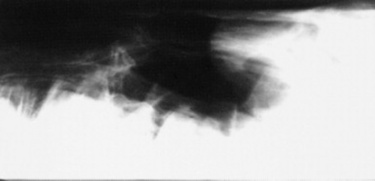

Confirmation requires endoscopy of the ethmoid conchae and skull radiography (Figs. 31-45 and 31-46); however, the origin and extent of the mass can be delineated more accurately by computed tomographic examination of the skull. Sinoscopy may be of diagnostic value in horses with ethmoid hematoma involving the paranasal sinuses without protrusion into the nasal cavity. Rarely, ethmoid hematoma infiltrates the nasal conchae; these lesions, identifiable by CT, may be missed by sinoscopy. Because ethmoid hematoma is bilateral in approximately 30% of affected horses, it is prudent to examine both the left and right ethmoidal conchae. The ethmoidal labyrinth is visible approximately 25 cm from the nares, with the endoscope positioned in the ventral nasal meatus and the viewing tip deflected dorsally. The rostral surface of the ethmoidal concha does not protrude beyond the caudal nasal cavity and has a bulbous shape and a moist pink to pale red mucosal covering.

Fig. 31-46 Lateral radiograph demonstrating an ethmoid hematoma.

Recognition of a discrete, often smooth-surfaced homogeneous radiodensity originating from the ethmoidal conchae and extending into the frontal, maxillary, or sphenopalatine sinuses or into the pharynx or nasal cavity is suggestive of an ethmoid hematoma. Radiography is beneficial in determining the extent of the hematoma and in identifying suspected ethmoid hematomas that are not visible by endoscopy; however, precise definition of the origin of any hematoma is difficult from radiographic projections. Small hematomas contained within the ethmoid labyrinth may not be visible on radiographs. Computed tomographic examination of the skull allows more accurate assessment of the origin of the ethmoid hematoma,1207,1209 allows determination of the extent of involvement of the paranasal sinuses and conchae, and facilitates surgical planning.